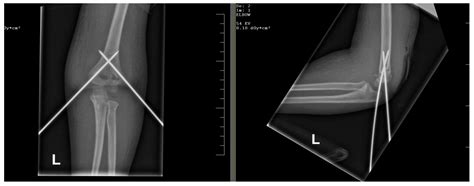

For displaced or completely displaced fractures (Type II and Type III), surgical treatment is often required to realign the bone fragments and stabilize the fracture. Common surgical procedures include:

• Closed reduction and percutaneous pinning (CRPP): This procedure involves manipulating the bone fragments back into place without open surgery and then inserting pins to hold them in position.

Surgical treatment aims to restore the normal anatomy of the elbow and promote healing. Post-operative care typically includes immobilization, pain management, and physical therapy to regain range of motion and strength.